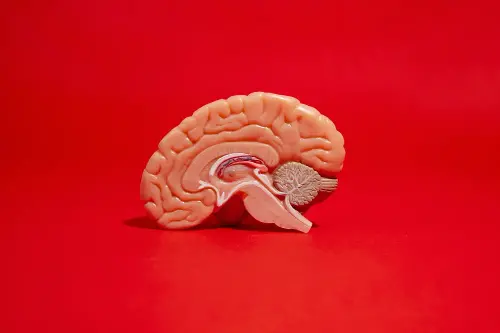

Types of brain cells

The researchers examined the neuron development with the help of a 3D brain tissue model. As per the researchers, there are two types of brain cells (or neurons). They include excitatory neurons which make up 80% of the neurons and help send signals. And then the remaining 20% are inhibitory neurons, which help regulate brain activity.

Among the inhibitory neurons, 60% are a special type called parvalbumin-positive neurons. They have a crucial role in determining how flexible the brain is. It is important as they influence how a person can learn new languages or adjust their senses. They are also associated with autism and schizophrenia. The scientists grew a large number of neurons in a lab. They added these cells inside miniature brain-like structures and kept them alive. This helped them observe a model that resembles the brain's functioning.